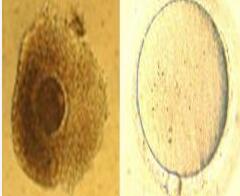

未成熟卵体成熟卵体外成熟技术

未成熟卵体外成熟技术(In Vitro Maturation,IVM)是试管婴儿领域的一项前沿技术,专门针对一些卵子成熟障碍的不孕患者,特别是那些顽固的多囊卵巢综合症、卵泡发育迟缓、卵巢过度刺激征的患者。

将未成熟的卵母细胞取出,在体外进行培养、受精,然后将胚胎移植到母亲子宫腔内生长。这种技术还可能避免药物和治疗的副作用,减少费用,降低促排卵的风险。